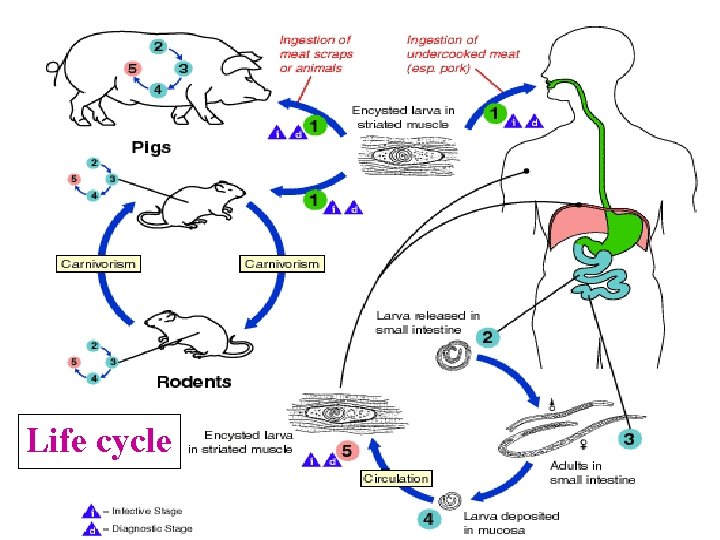

Life cycle